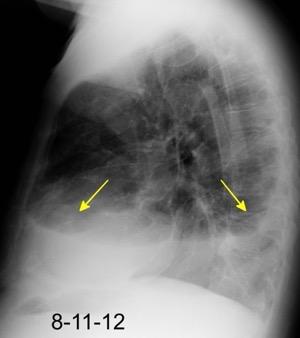

100. TUMOR FANTASMA

En relación con trasudados tabicados. Insuficiencia cardiaca

Derrame pleural “encapsulado”

“Tumor fantasma”

Asociado a fallo cardiaco. ( “Pleuritis adhesiva”). Buch KP. Chest. 2000